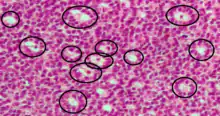

Call-Exner bodies

Call–Exner bodies, giving a follicle-like appearance, are small eosinophilic fluid-filled punched out spaces between granulosa cells.[1] The granulosa cells are usually arranged haphazardly around the space.

They are pathognomonic for granulosa cell tumors.

Histologically, these tumors consists of monotonous islands of granulosa cells with "coffee-bean" nuclei. That same nuclear groove appearance noted in Brenner tumour, an epithelial-stromal ovarian tumor distinguishable by nests of transitional epithelial cells (urothelial) with longitudinal nuclear grooves (coffee bean nuclei) in abundant fibrous stroma. [2]

They are composed of membrane-packaged secretion of granulosa cells and have relations to the formation of liquor folliculi which are seen among closely arranged granulosa cells.